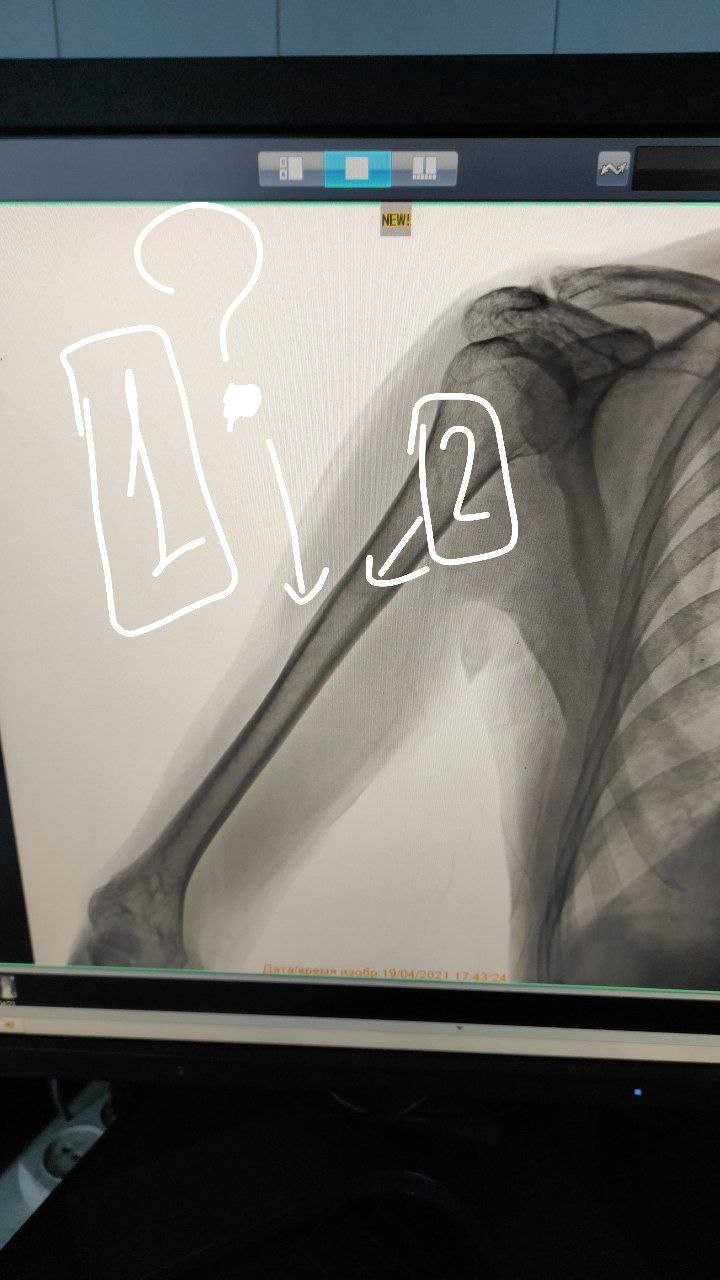

Всем доброго вечера.

Мужчина 50 лет

Жалобы: Боли верхней части левого плеча

Коллеги изменения визуализируется ?

Нет, не визуализируется

Как обяснить эти области тогда ? 🤔

Я даже не понимаю, что вам там не нравится

Оставьте плечико в покое. Это в норме там.